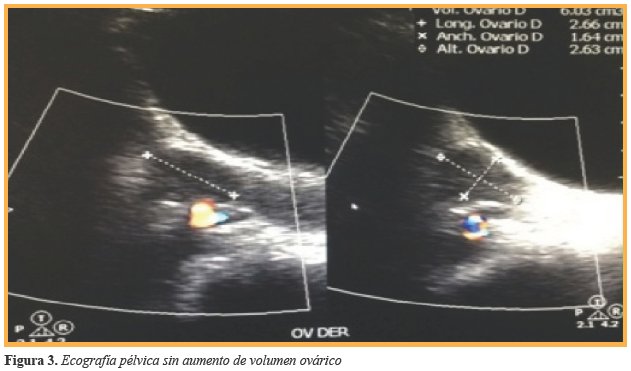

Debido a antecedentes y sintomatología referido por la paciente, se inició protocolo de estudio. El reporte de bioquímicos fue glucosa 90 mg/dl, Hb1Ac 5,2%, insulina 16,5 μUl/ml, HOMA-IR 3,66; triglicéridos 90 mg/dl, colesterol total 152 mg/dl, HDL 38 mg/dl, LDL 96 mg/dl, ALT 21 u/1, sin reunir criterios para Diabetes Mellitus ni para Síndrome Metabólico, por lo que se decidió completar el abordaje inicial realizando pruebas de función tiroidea ante la sintomatología digestiva y ginecológica referida por la paciente, obteniendo como resultados los mencionados en la (Tabla 1). Ante la detección de hipotiroidismo primario y debido a que la principal etiología es autoinmune, se complementó protocolo de abordaje con realización de anticuerpos, destacando la elevación de: anticuerpos antitiroglobulina 0,90 Ul/ml, anticuerpos antiperoxidasa 359,40 Ul/ml, ANA 1:100, concluyendo diagnóstico de Tiroiditis de Hashimoto. Debido al hallazgo de bocio, se realizó ultrasonido de cuello con reporte de incremento en el tamaño de los lóbulos tiroideos a expensas de lóbulo derecho con nodulos tiroideos sin calcificación ni vascularidad incrementada (Figura 2) la paciente cursaba con irregularidad menstrual por lo que se solicitó ultrasonido pélvico el cual fue reportado sin alteración (Figura 3).

Los niveles de hormonas tiroideas mejorarán al lograr pérdida ponderal superior al 10% del peso inicial sumado al tratamiento con levotiroxina, además de mejoría de la insulinorresistencia y del resto de las comorbilidades8. La paciente mostraba alteraciones en su ciclo menstrual, esto relacionado con la presencia de receptores de hormona tiroidea a nivel ovárico, afectándose la esteroidogénesis y la acción de la aromatasa, produciéndose hiperprolactinemia en el caso del hipotiroidismo y aumento de la ovulación seguido de anovulación persistente en el caso del hipertiroidismo, y según lo reportado por Jahn G. et al6, existe una asociación entre la disfunción tiroidea y la incidencia aumentada de abortos, irregularidades menstruales y fertilidad subnormal debido a la reactividad cruzada de los anticuerpos anti tiroideos bloqueantes sobre los receptores de gonadotrofinas, impidiendo la acción de éstas sobre el ovario6; sin embargo, en el contexto de ser una adolescente con obesidad, se descartaron complicaciones ginecológicas asociadas a la misma, como el síndrome de ovarios poliquísticos, ya que la paciente no reunió los criterios de Rotterdam que justificarían dicho diagnóstico. Para evitar tratamiento farmacológico innecesario, se recomienda ser cauto al momento del diagnóstico en estos pacientes, siempre tomando como base un ultrasonido correlacionado con el nivel de anticuerpos9, en el contexto de un paciente en que se detecte hipotiroidismo primario, considerar inicio de tratamiento sustitutivo con levotiroxina cuando los niveles de TSH sean mayores a 10 mIU/1 o menores a esta cifra si se encuentra con manifestaciones clínicas de hipotiroidismo10. Sin embargo, estas cifras han sido extrapoladas de población adulta, ya que no se cuenta aún con estudios suficientes que hablen de las cifras ideales para inicio de manejo con tiroxina en adolescentes11. Posterior al inicio del tratamiento de sustitución, se espera normalización de valores bioquímicos y remisión o mejoría en la sintomatología de hipotiroidismo, evidenciado por la evolución favorable de la paciente tras el comienzo del manejo farmacológico con levotiroxina, aunado a que favoreció el control ponderal. Por ello, es importante continuar el seguimiento de la paciente para evaluar si el tratamiento farmacológico puede condicionar cambios ultrasonográficos a largo plazo y vigilar la presencia de enfermedad tiroidea crónica y así contribuir más adelante al manejo de otros pacientes.